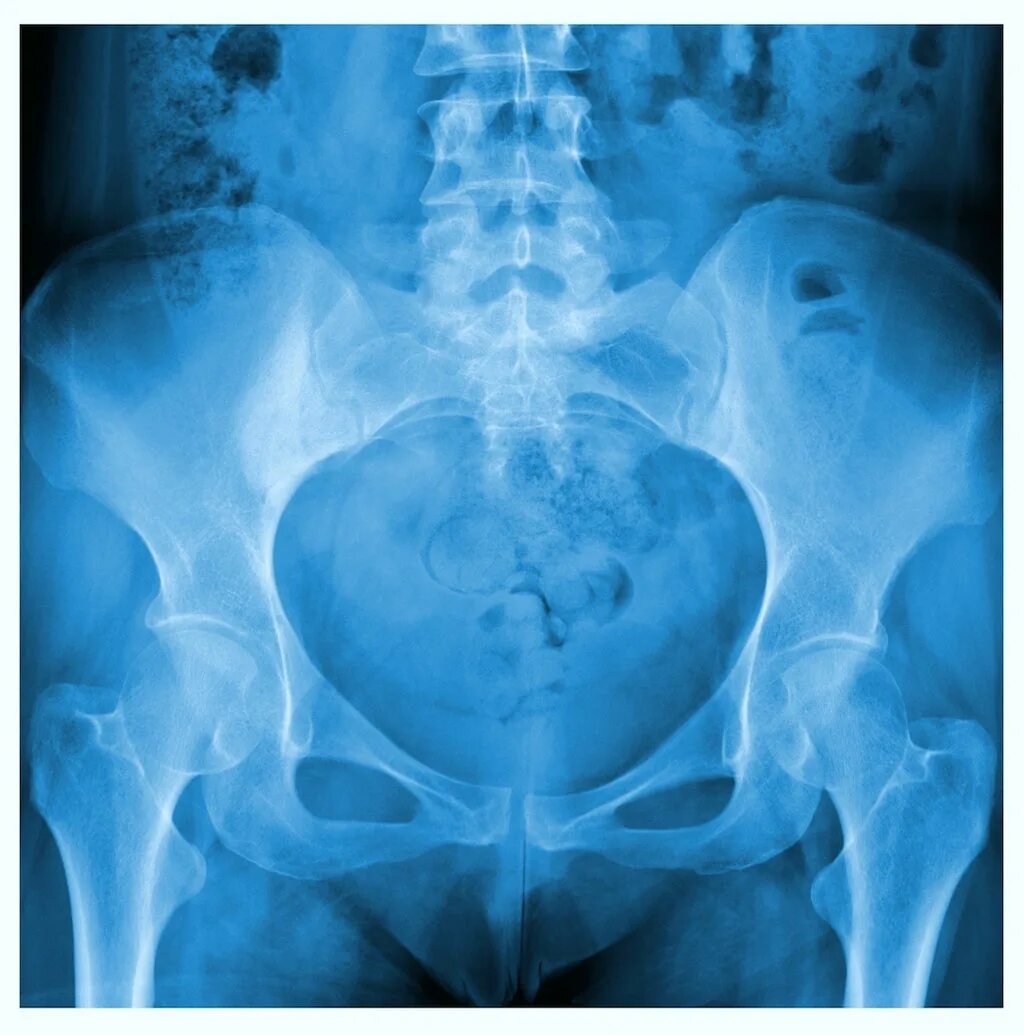

Таза абдоминально